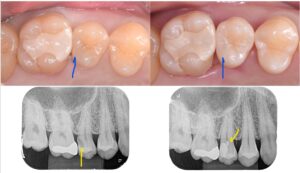

VPT により壊死した部分の神経を取り、生きている神経を残せるようになりました。

マイクロスコープ(顕微鏡)で拡大して神経をみながら壊死部分を判断して除去、

MTAセメントで封鎖することにより生きている神経を保護します。